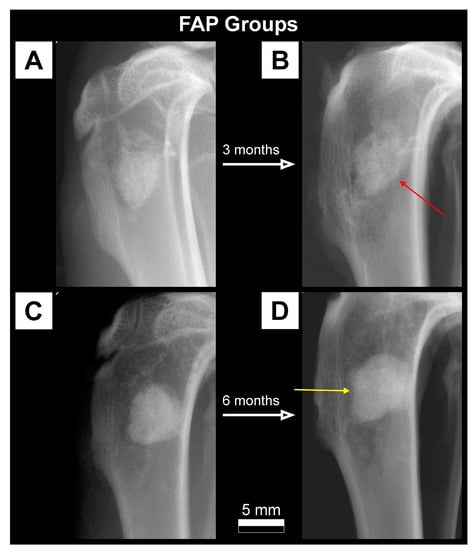

2.3.1. X-ray Imaging—Conventional Radiography

3.1. Qualitative Analysis of Bone Substitute Materials